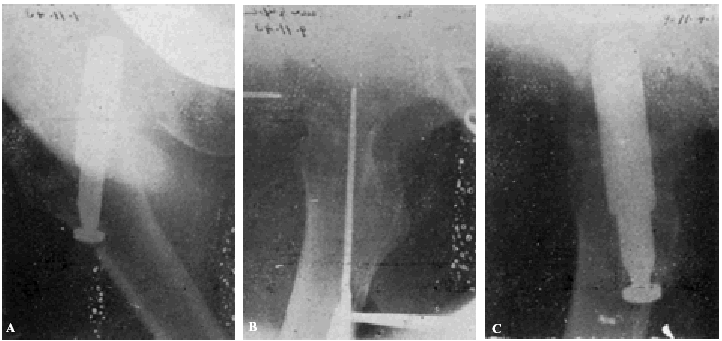

Fracaso número 2(observación número 2). F. S., setenta años4. Ingresa en el servicio con una fractura mediana del cuello femoral izquierdo. Osteosíntesis extraarticular (fig. 3. A y B). La impactación no ha resultado perfecta.

Figura 3. A: obs. núm. 2. El clavo no penetra suficientemente y la impactación, salvo en la parte superior de la línea de fractura, es muy defectuosa. B: obs. núm. 2. La posición del clavo es buena. C: obs. núm. 2. El clavo tiende a ser expulsado hacia fuera y apenas penetra en la cabeza femoral.

A los veinte días de la intervención pasa el enfermo a su domicilio, recomendándole que continúe en la cama. Pasado un mes vemos nuevamente al enfermo, el cual nos manifiesta que anda con mucha más dificultad que en los primeros días de permanecer en su domicilio, que fue cuando, por no haber interpretado bien nuestras indicaciones, comenzó a emprender la marcha. La radiografía (fig. 3. C) demuestra que el clavo apenas penetra en la cabeza femoral. A los ocho días hacemos otra radiografía (fig. 4. A), observándose que el trocáncer ha ascendido, a pesar de continuar guardando cama el enfermo. Ingresa nuevamente en el servicio, donde, con anestesia raquídea, retiramos el clavo, reduciendo las fracturas y volviendo a colocar un clavo más largo en buena dirección (fig. 4. B). Una radiografía practicada siete años y medio más tarde demuestra la no consolidación de la fractura, trastornos tróficos en cuello y cabeza femoral y que el cabo ha penetrado en el fondo de la cavidad cotiloidea, en donde ha labrado una cavidad (fig. 4. C).

Figura 4. A: obs. núm. 2. El trocánter ha ascendido francamente con relación a la radiografía anterior. El clavo tiende a salir de la cabeza por su parte superior. B: obs. núm. 2. Se extrajo el clavo y se colocó otro. El nuevo clavo está colocado en buena dirección, pero la reducción no es perfecta. C: obs. núm. 2. El clavo ha penetrado en el fondo de la cavidad cotiloidea, en cuyo lugar ha labrado una cavidad. Trastornos tróficos en cuello ycabeza femoral. El cuello del fémur ha desaparecido casi completamente.

En este caso el fracaso se debe a que la impactación no fue perfecta, y sobre todo, a haber el enfermo iniciado la deambulación al mes de intervenido, a pesar de que nosotros le ordenamos que guardara cama.